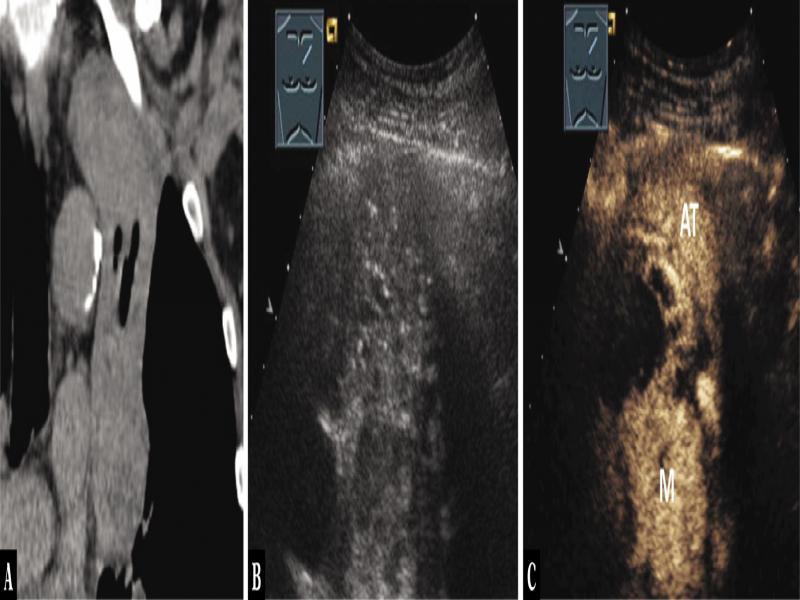

Fig. 13.

A 58-year-old male patient with thoracic pressure sensation and a mediastinal tumor in the anterior mediastinum on computer tomography (A). A history of renal carcinoma was known. Thoracic ultrasound indicated a dumbbell-shaped, centrally hypoechoic and peripherally inhomogeneous echogenic tumor (B), which on contrast-enhanced ultrasound shows a marked enhancement centrally and peripherally, similar to that in peripheral atelectasis (AT) and central metastasis (M) (C). The diagnosis of a metastasis from renal cell carcinoma was histologically confirmed